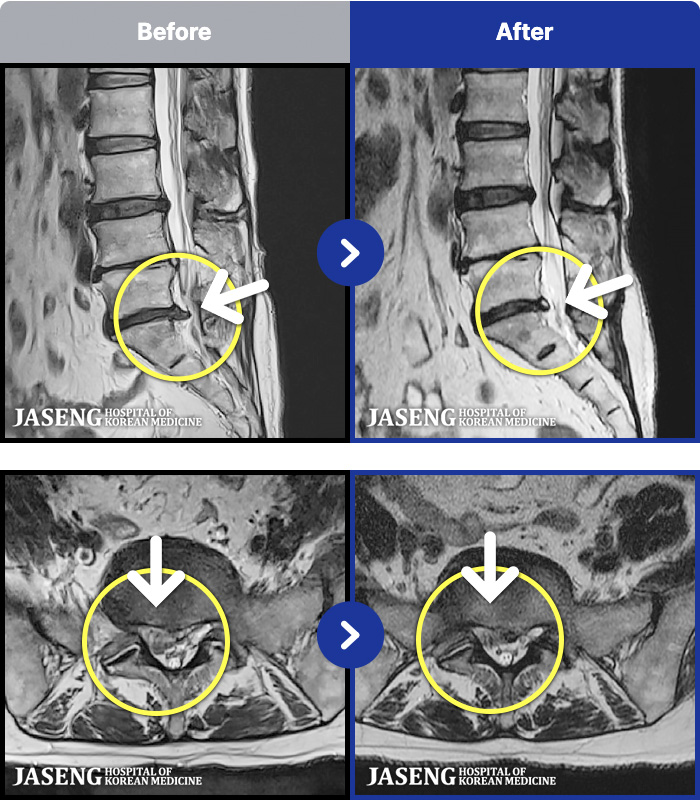

63 MRI ũ ʸ Ȯϼ.

ȯںп Ǹ ǿ ԿǾ, ο ġ ۿ Ƿ ġḦ Ͻñ ٶϴ.